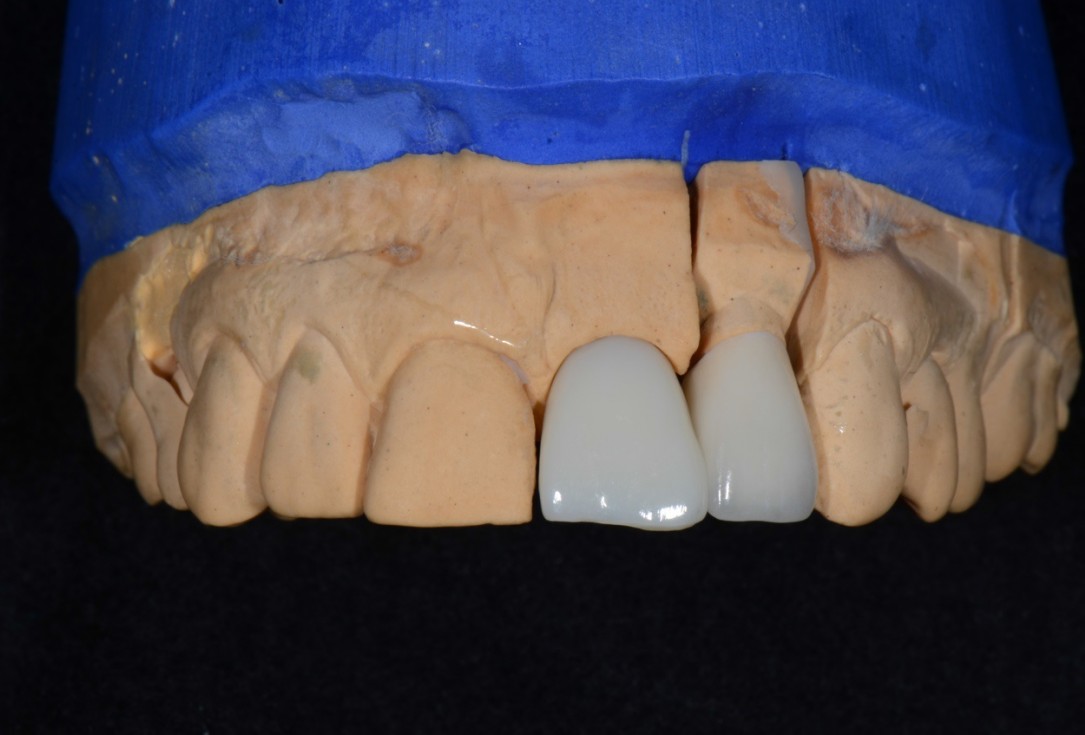

14/16 - Implant screwed crown for restoration of 21 and full porcelain crown for 22

Socket preservation with cerabone® - Dr. R. A. Nader